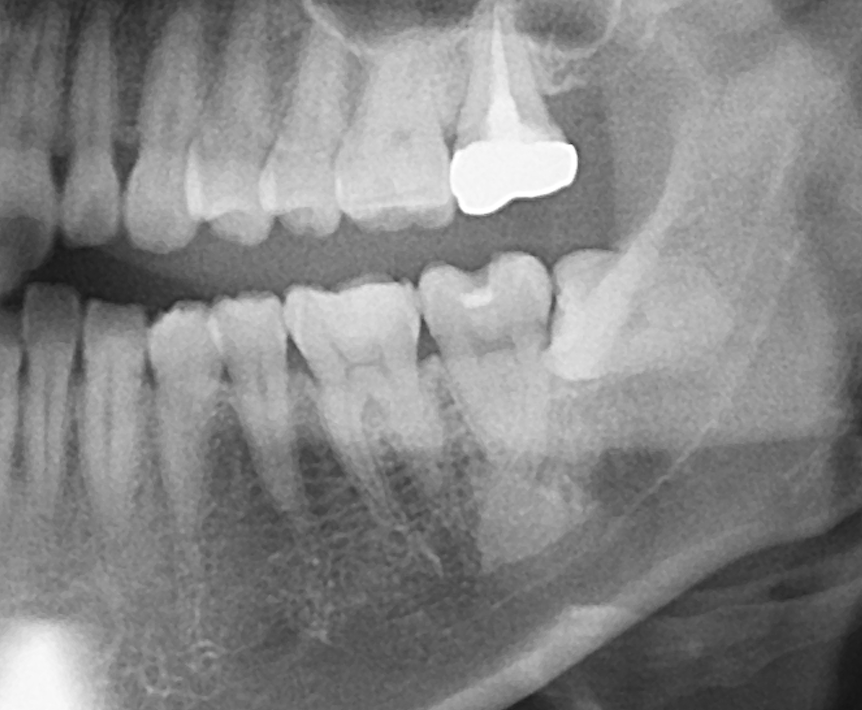

◎歯科用CT画像とレントゲン写真の違いは?

写真は同一部位のレントゲン写真とCT画像です。レントゲン写真は顎骨の形態や走行する神経の位置、歯が生えている方向把握することはできても2次元的な位置関係でしか把握できません。つまり歯や神経の位置がわかっていても実際にどのくらいの位置関係にあるのかを正確に判断することはレントゲン写真では不可能なわけです。しかし、歯科用CT画像では顎骨の形態や走行する神経の位置、歯の生えている方向、さらには骨密度の状態を3次元的に画像化する事が可能なため、より正確な診断する事ができます。